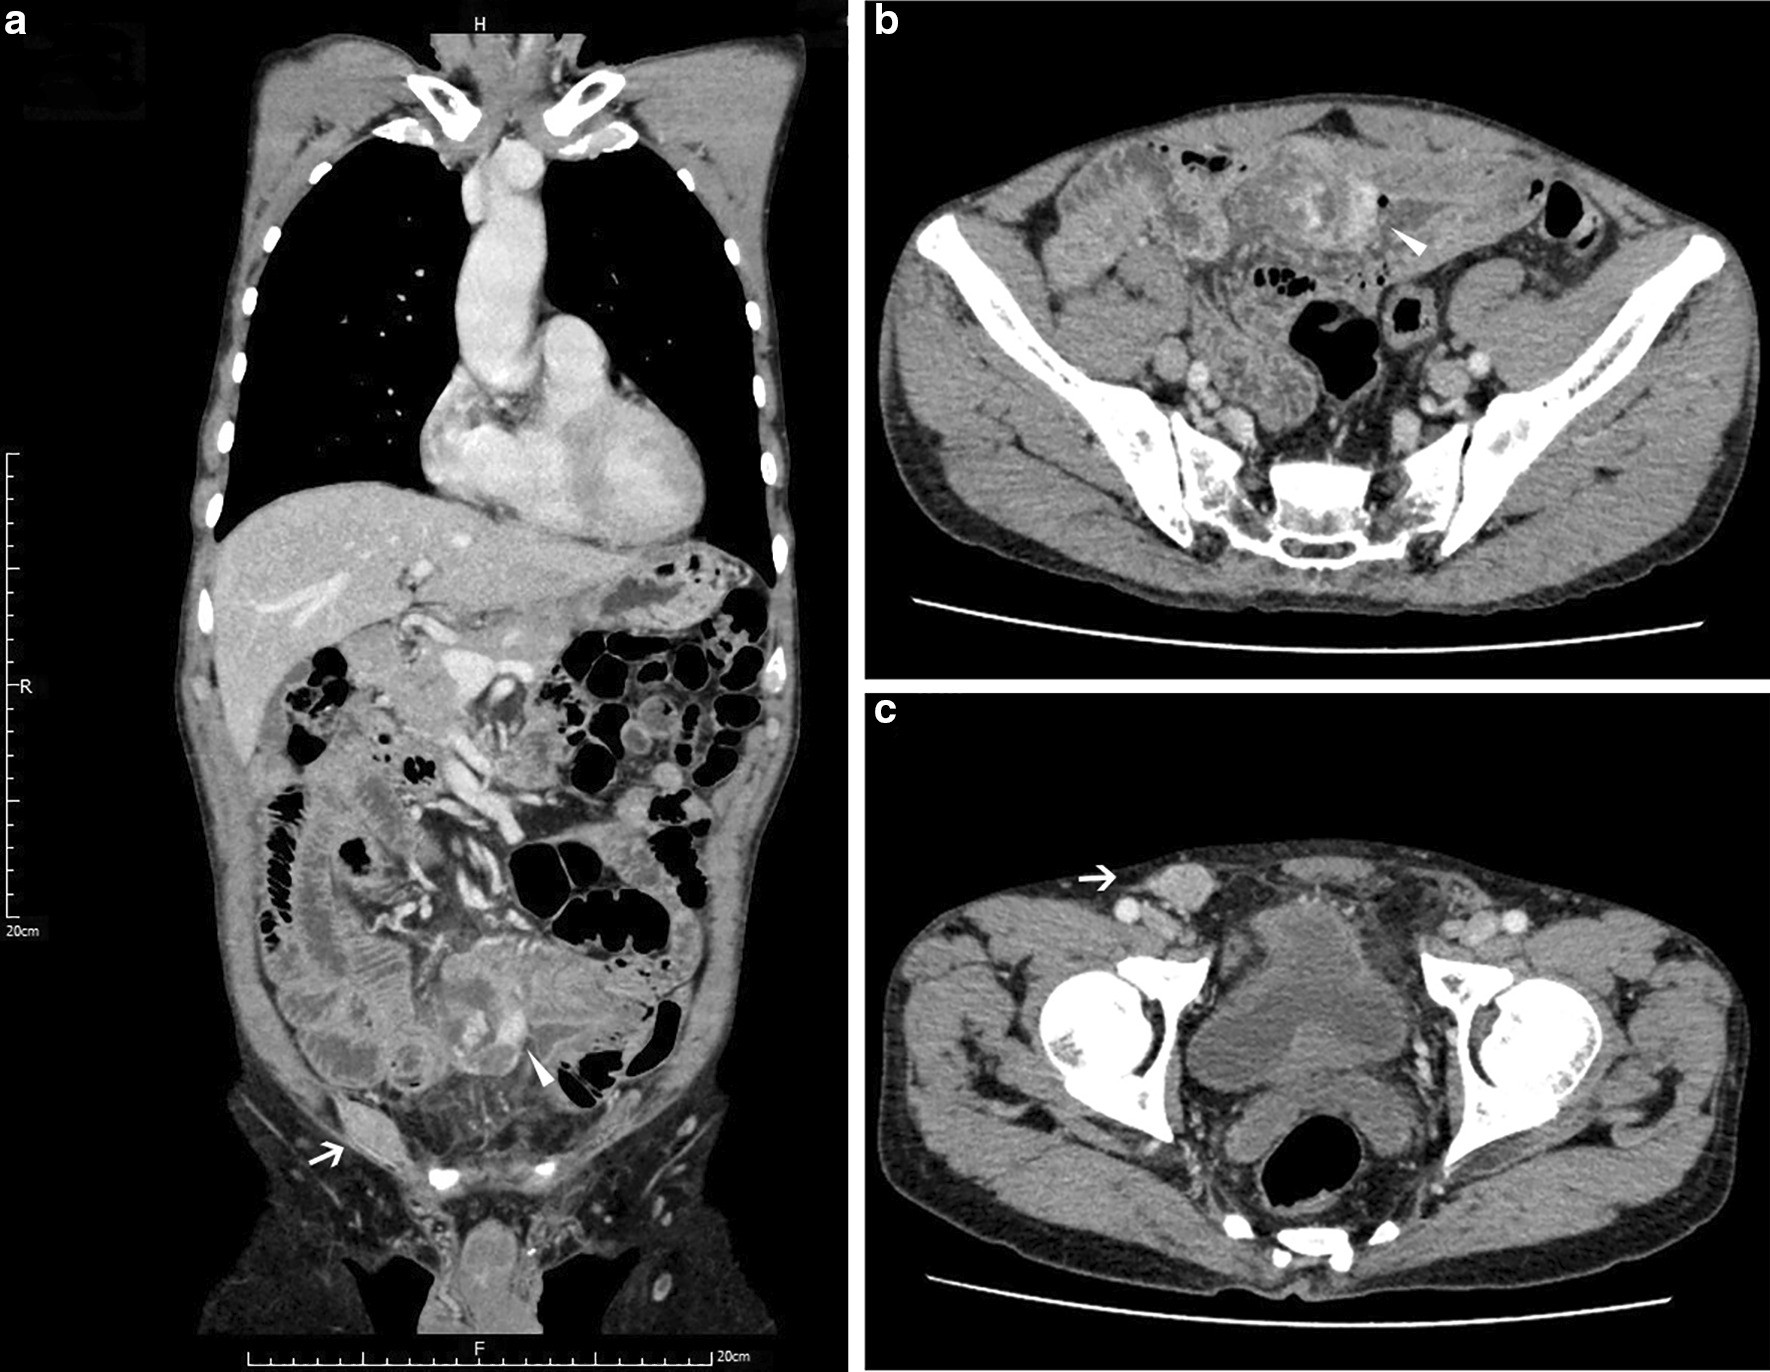

Fig. 1

The radiological finding of the current case. CT images in the venous phase indicating a huge mass in the small intestine and an isolated inguinal mass in the right groin. Both masses were contrast-enhanced, without distinct lymph node metastasis in the abdomen. a Coronal plane rebuilt scan; b, c Horizontal plane scans; Arrows and triangle shapes indicating inguinal and intra-abdominal mass, respectively